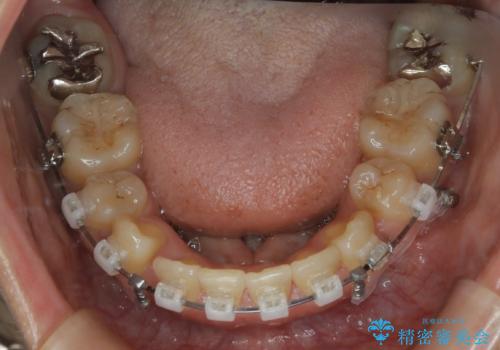

前歯を後ろに下げたい ワイヤー矯正(クリア装置)

- 矯正装置

- クリア装置

口元の突出感の改善や歯の移動量などを考慮し、抜歯を伴うワイヤー矯正での治療を選択しました。

抜歯を行うことで前歯を後ろへ下げるスペースを獲得し、口元の突出感や歯のガタつきを改善していきました。